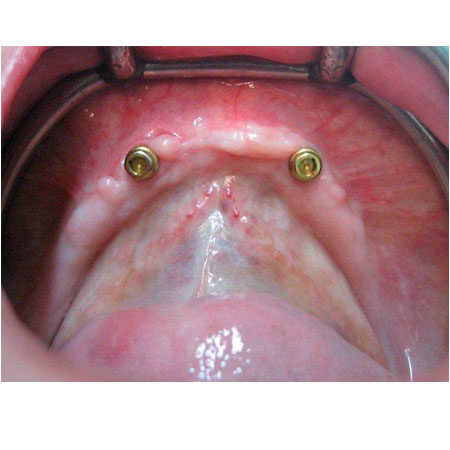

Nº3 DENTADURA COMPLETA ESTABILIZADA CON IMPLANTES

Una periodontitis muy avanzada hizo recomendable la extracción de todos los dientes y la rehabilitación de toda la dentadura mediante implantes y prótesis cerámica.